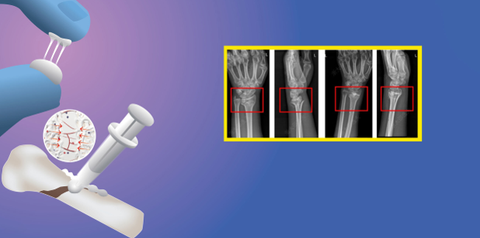

Mô phỏng hoạt hình về quá trình ghép xương gãy bằng Bone 02 Lấy cảm hứng từ thiên nhiên Tại Bệnh viện Sir Run Run Shaw, tỉnh Chiết Giang (Trung Quốc), một nhóm nghiên ...